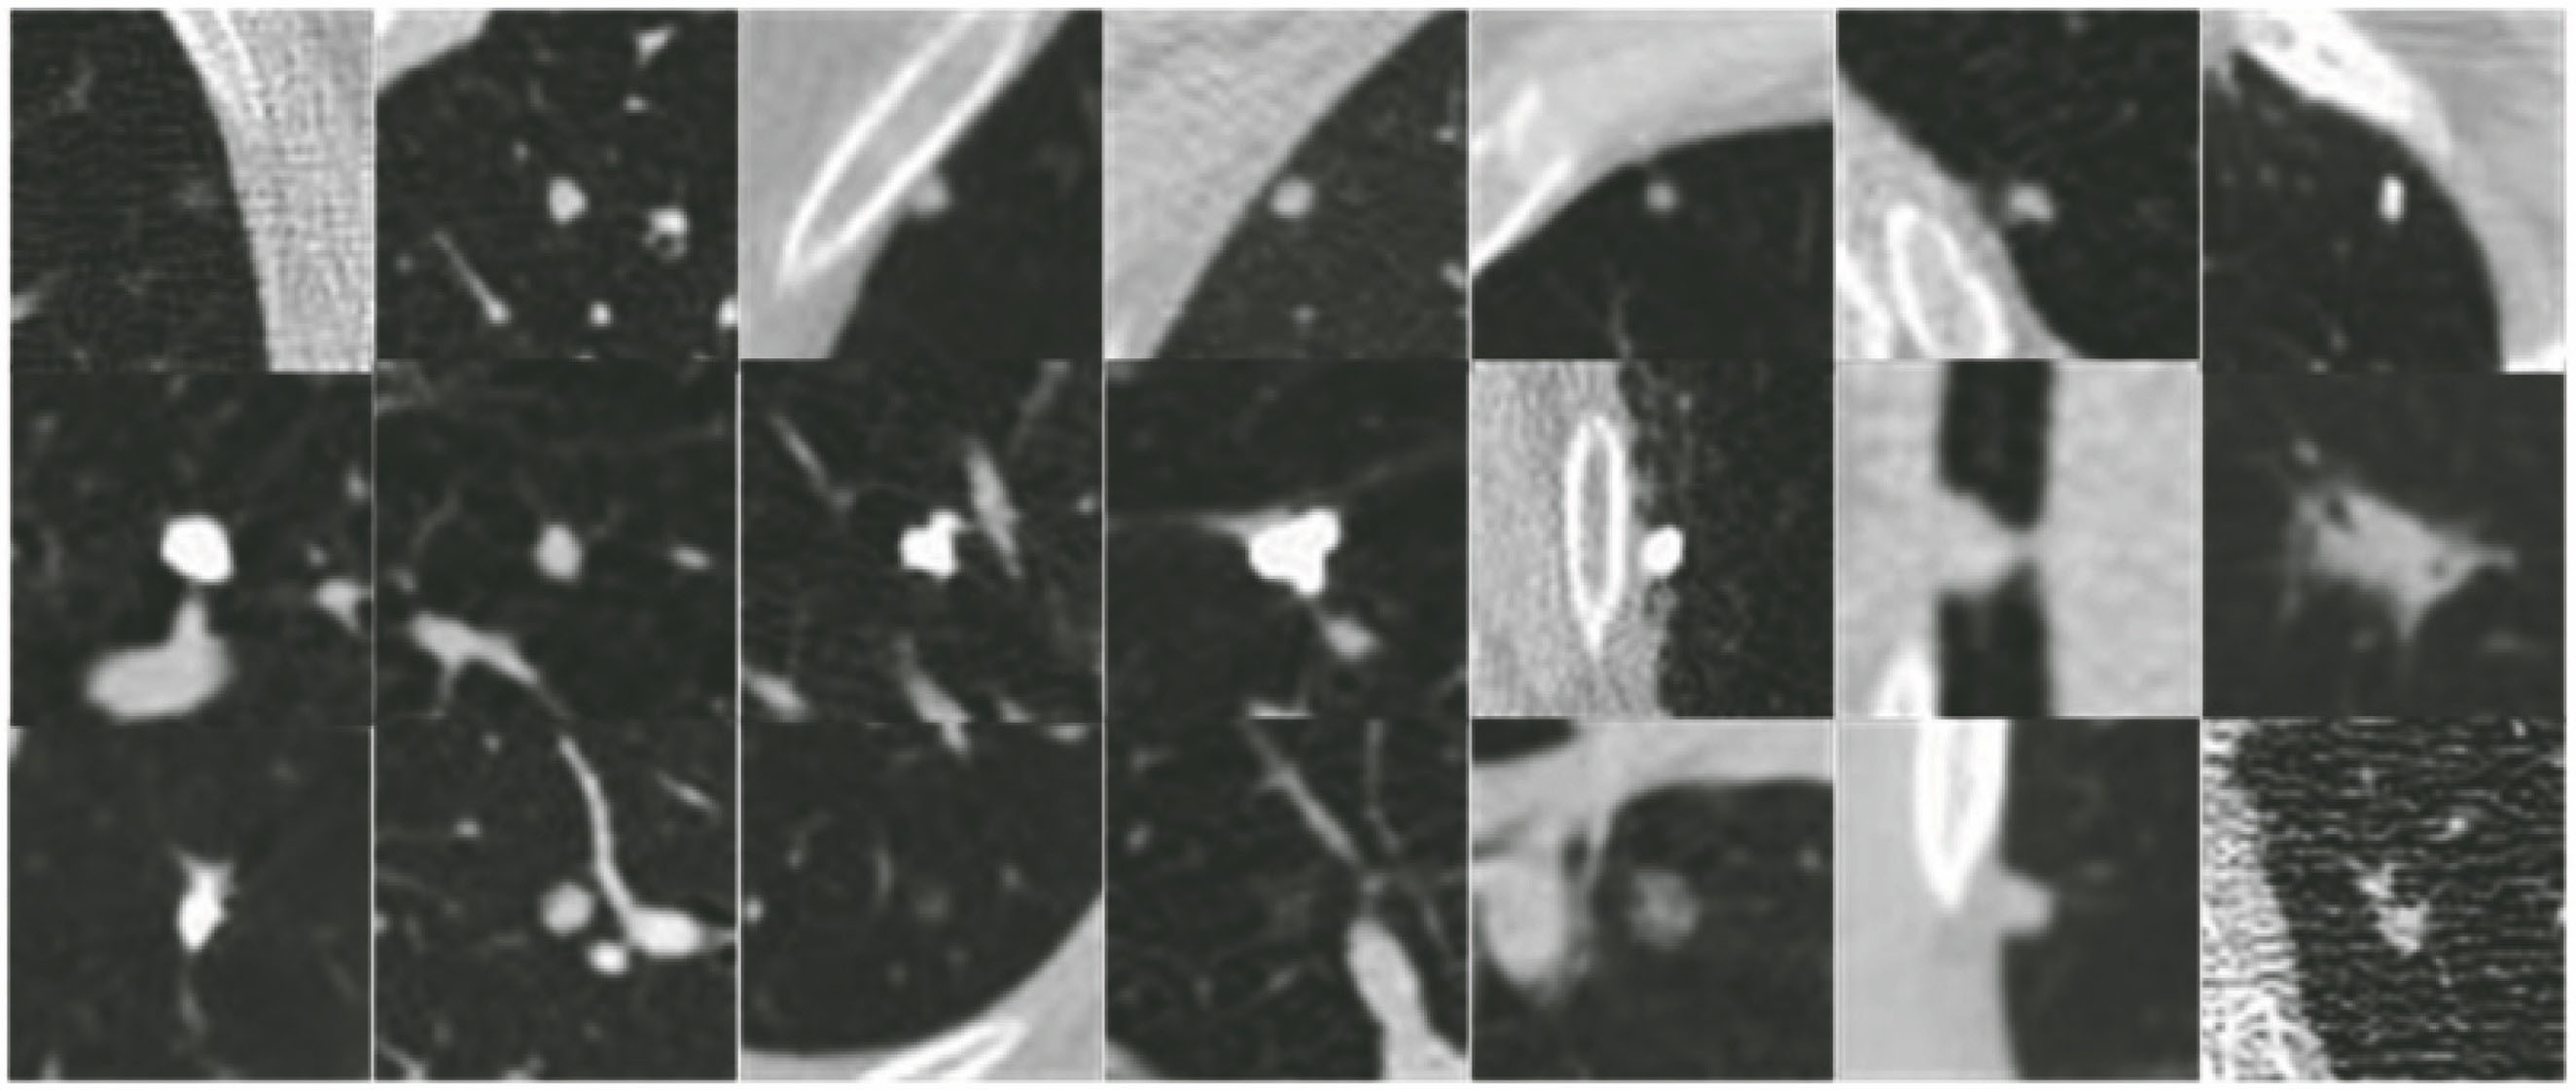

图 5. 数据库中不同尺寸结节的图像。(a)小结节;(b)中等结节;(c)大结节

Fig. 5. Images of nodules with different sizes in the database. (a) Small nodules; (b) middle nodules; (c) big nodules